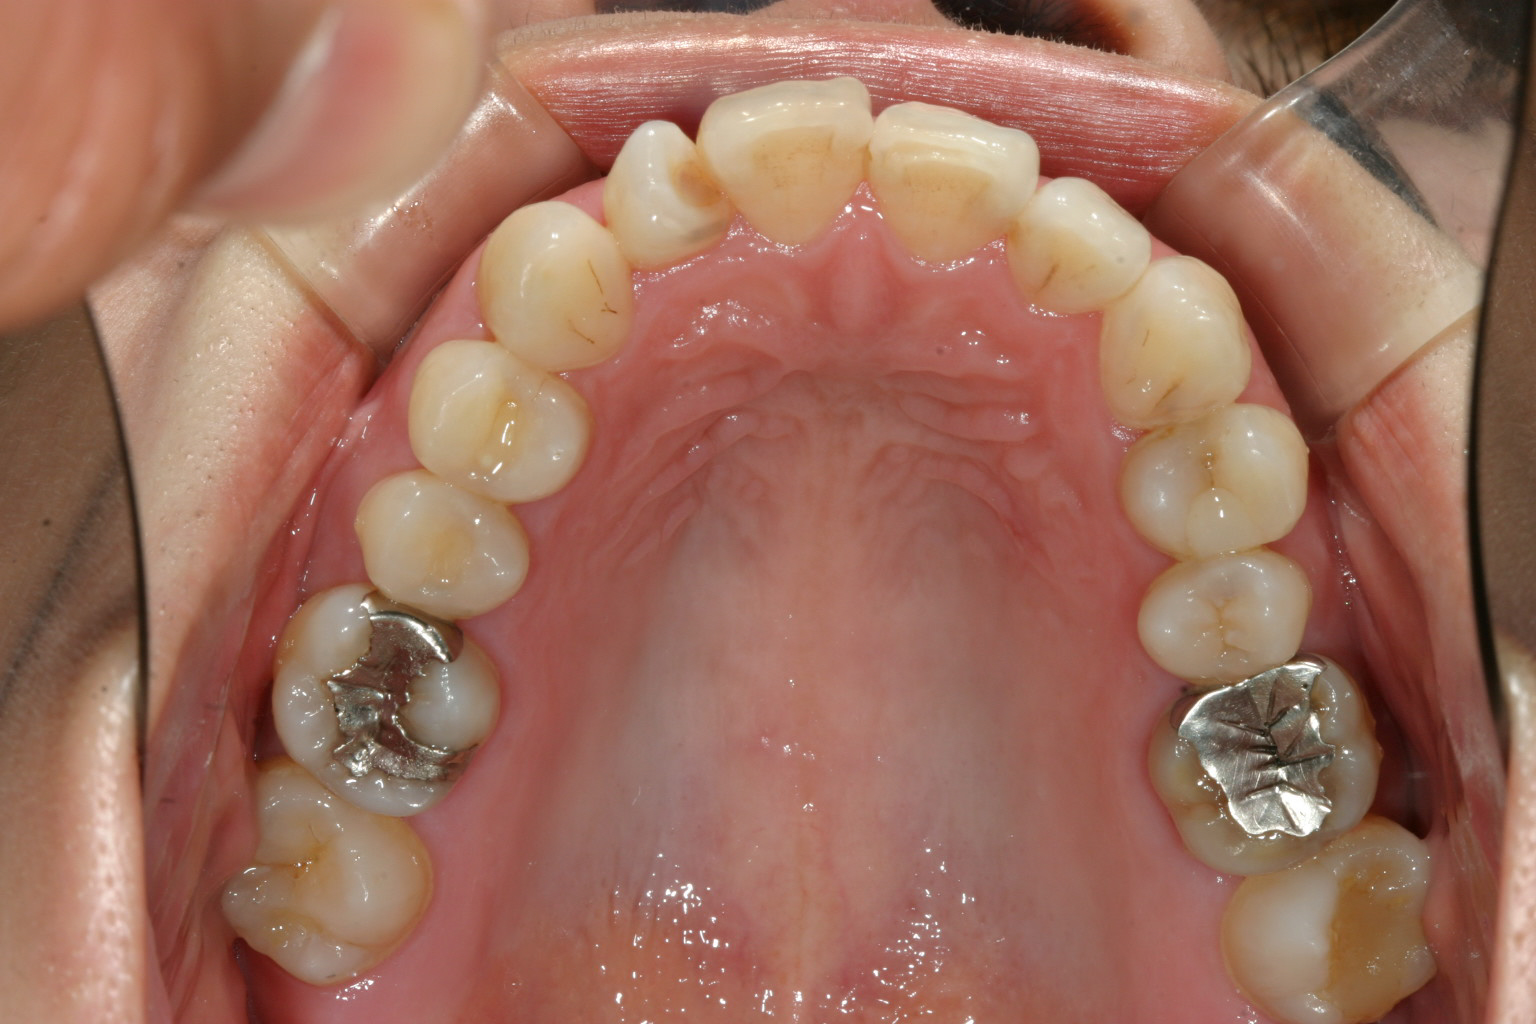

出っ歯観改善の為、左の小臼歯1本だけ抜歯して頂きました。

今回は出っ歯観改善の為、左側上顎小臼歯を1本だけ抜歯しました。

あとは上顎の歯のねじれ改善、下顎の舌側転移も難なく出っ歯も改善しました。